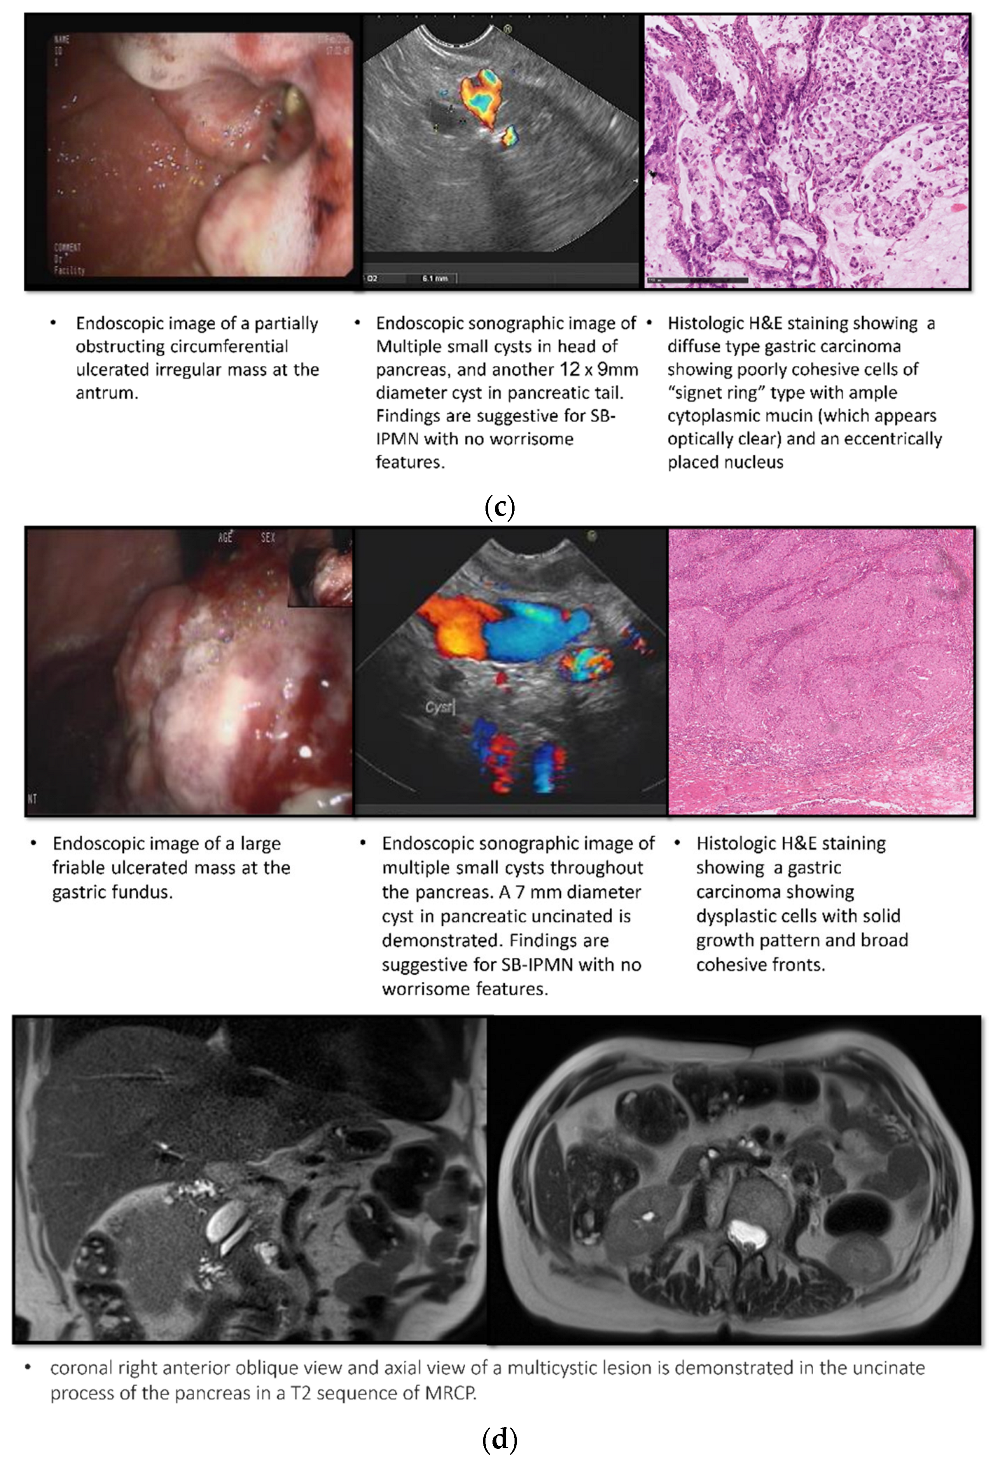

Table 3 provides a comprehensive description of all nine cases of gastric cancer identified in our cohort, including both patients with known IPMNs and those in the control group. In the IPMN group, four cases of gastric cancer were diagnosed during the initial EGDs. These cases presented with various characteristics, such as a large ulcerated infiltrating mass at the gastric body (Figure 1a), an infiltrating mass with contact oozing at the gastric body (Figure 1b), a partially obstructing, circumferential, ulcerated, irregular mass at the gastric antrum (Figure 1c), and a large friable ulcerated mass at the gastric fundus (Figure 1d).

Figure 1.

Endoscopic, sonographic, radiologic, and histologic imaging of IPMN patients diagnosed with gastric cancer in their first EGD. (a) Case 1; (b) Case 2; (c) Case 3; (d) Case 4.